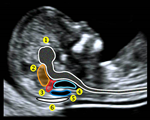

El ultrasonido como parámetro pronostico gestacional, ha revolucionado la obstetricia, aprenderás a realizar los estudios hemodinámicos fetales. Ecocardiografía fetal, Neurosonografía y los diferentes tamizajes. |

El uso de parámetros internacional para la emisión del estatus fetal y su pronostico es eje fundamental de éste diplomado. |